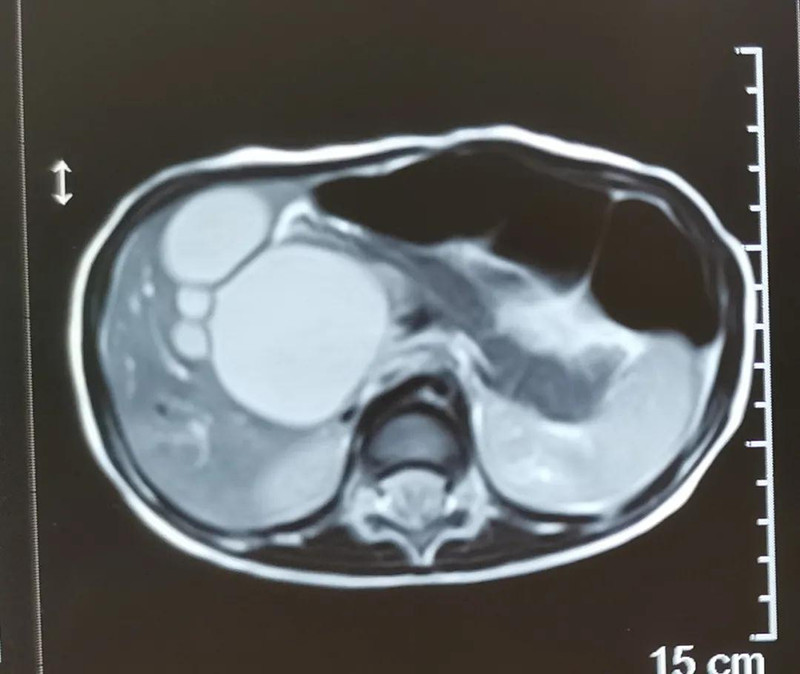

最近半个月,长春市26个月女宝馨馨(化名)脸色不好,全身发黄严重,还伴随发烧。9月23日,馨馨被家人带到蜜桃视频 诊治。经检查,馨馨全身发黄是因为患有黄疸,而黄疸的出现是因为胆总管发生病变,“胆总管呈现囊性扩张,下边出口被堵住,胆汁进不到肠腔里,导致孩子出现黄疸、肝功不好、白土便症状。而且胆总管胀大后,还有癌变的风险,”普外、新生儿外科主任崔钊说,馨馨需要尽快手术。为了减少损伤,崔钊主任团队制定的方案是单孔腹腔镜下胆总管囊肿根治手术。

术前准备完毕。 9月25日,馨馨进入手术室。由崔钊主任带队,按照术前设计的方案,经过8个小时的奋战,手术成功了。馨馨肝总管以下病变的胆总管及胆囊全部切除,肝总管断面与肠管吻合接上,让胆汁直接流到肠腔里,帮助消化。如术后不出现胆瘘、肠瘘,没有梗阻,馨馨以后就可以正常生活了。目前馨馨恢复得很好,黄疸渐渐缓解,肝功正常,白细胞也降下来了,排气、排便都没问题,引尿管里也没有异常东西。